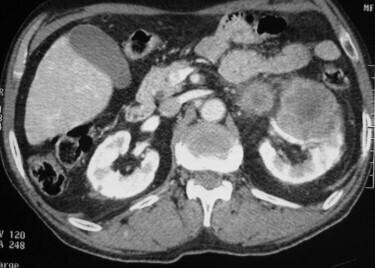

Question 5 - Quelle interprétation faites-vous de cette tomodensitométrie abdominopelvienne (une ou plusieurs réponses exactes) ?

L’examen montré ici est une TDM abdominopelvienne en coupe transversale avec injection de produit de contraste au temps veineux.

On retrouve sur cette coupe :

• une volumineuse masse tissulaire rénale gauche.

On ne retrouve pas sur cette coupe :

• de thrombus veineux (veine rénale ou veine cave inférieure) ;

• d’adénopathies ;

• de seconde tumeur rénale gauche ou droite ;

• de nodule hépatique ou pulmonaire.

Au total, sur cette coupe, on conclut à un cancer localisé du rein gauche.

L’examen complet de la TDM ne retrouve pas d’autres anomalies.